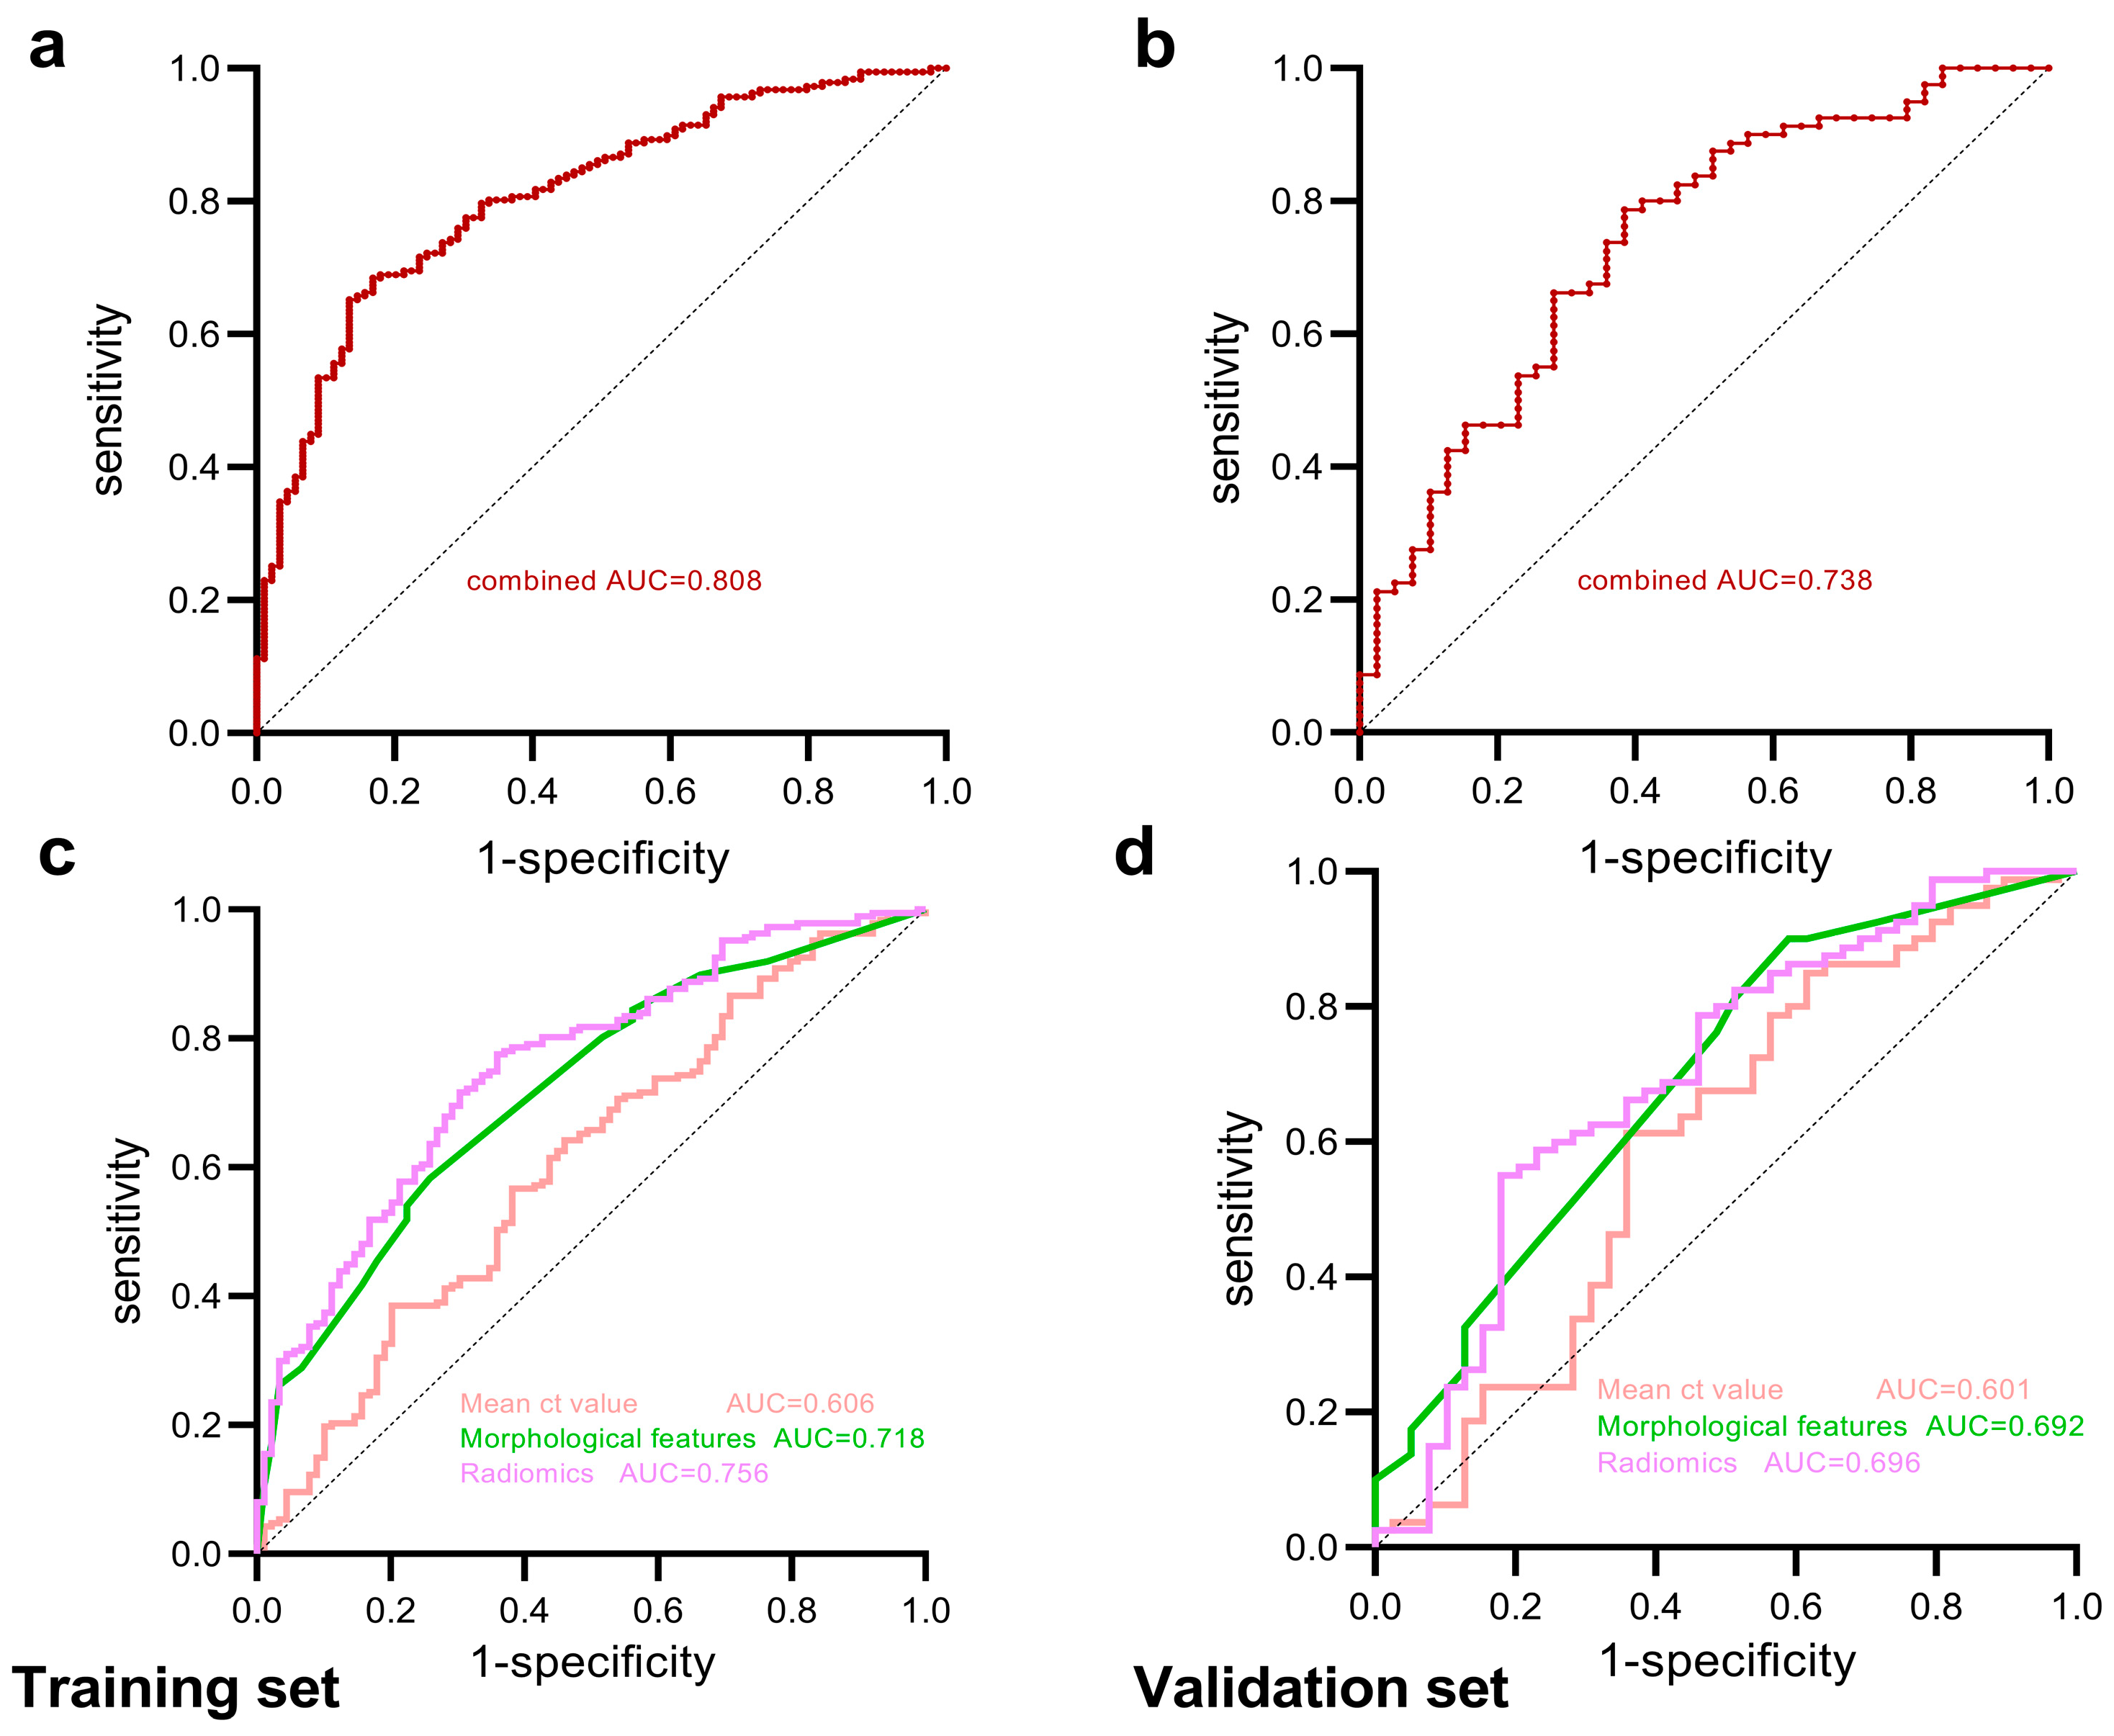

3.3. Construction and Diagnostic Performance of Predictive Models

| Models | Area | 95% CI | Specificity | Sensitivity | NPV | PPV | FDR | FPR | |

|---|---|---|---|---|---|---|---|---|---|

| Training set | Mean CT value | 0.606 | 0.534–0.678 | 0.618 | 0.567 | 0.404 | 0.757 | 0.243 | 0.382 |

| Morphological features | 0.718 | 0.656–0.781 | 0.742 | 0.583 | 0.458 | 0.826 | 0.174 | 0.258 | |

| Radiomics features | 0.756 | 0.696–0.815 | 0.640 | 0.775 | 0.576 | 0.819 | 0.181 | 0.360 | |

| Combined | 0.808 | 0.755–0.861 | 0.865 | 0.652 | 0.542 | 0.910 | 0.090 | 0.135 | |

| Validation set | Mean CT value | 0.601 | 0.486–0.717 | 0.641 | 0.613 | 0.446 | 0.778 | 0.222 | 0.359 |

| Morphological features | 0.692 | 0.589–0.795 | 0.410 | 0.900 | 0.667 | 0.758 | 0.242 | 0.590 | |

| Radiomics features | 0.696 | 0.590–0.802 | 0.821 | 0.550 | 0.471 | 0.863 | 0.137 | 0.179 | |

| Combined | 0.738 | 0.641–0.835 | 0.615 | 0.788 | 0.585 | 0.808 | 0.192 | 0.385 |

| Models | Statistic | p | 95% Confidence Interval |

|---|---|---|---|

| Combined vs. Radiomics | 2.509 | 0.012 | 0.011 to 0.093 |

| Combined vs. Morphological | 3.500 | <0.001 | 0.039 to 0.139 |

| Combined vs. Mean CT value | 5.016 | <0.001 | 0.123 to 0.281 |

| Radiomics vs. Morphological | 0.881 | 0.378 | −0.046 to 0.119 |

| Radiomics vs. Mean CT value | 3.561 | <0.001 | 0.067 to 0.232 |

| Morphological vs. Mean CT value | 2.548 | 0.011 | 0.026 to 0.199 |